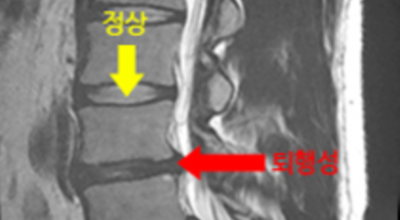

허리디스크는 디스크의 퇴행성 변화나 외상에 의해 발병할 수 있지만 현대인의 경우 인체적 과부하로 인해 발병하는 경우도 있 다고 알려져 있는데, 대개 잘못된 자세나 운동부족, 잘못된 운동 자세가 원인이지요. 허리디스크는 보통 20~40대에 많이 발생하는데, 유전적 요인이나 큰 신장, 비만 흡연 사례 등이 허리디스크 발생 위험을 높이 다고 알려져 있어요.

디스크는 일어선 상태에서는 중력을 받아 납작해져서 바깥쪽으로 약간 볼록한 형태가 된다고 합니다. 디스크는 그 특수한 구조 때문에 웬만한 힘이 가해져도 효율적으로 쿠션 역할을 할 수 있겠습니다. 그러나 급작스럽게 무거운 물건을 들어 올리거나, 부자연스러운 자세를 오랜 시간 취하면 디스크에 무리한 힘이 가해지면서 디스크가 밖으로 돌출이 되게 돼요. 심한 경우 디스크를 감싼 막이 터지면서 그 안에 있는 수핵이 튀어나오게 돼요.

디스크는 대개 후방이나 후외방으로 돌출되는데 이때 바로 곁에 있는 신경을 누르게 된다고 합니다. 돌출된 디스크는 척추의 어느 부위에나 일어날 수 있어요. 목에 생기면 '목 디스크', 등에 생기면 '등 디스크', 허리에 생기면 '허리 디스크'라고 부른다고 합니다.